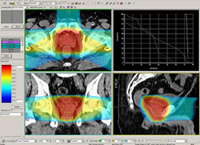

En 1980 se comenzó a utilizar el TC que permite una mayor precisión y disminuye la toxicidad en la vejiga, recto e intestino delgado. De este modo en los años 80 y 90 pudieron aumentarse las dosis hasta 75-79 Gy. En los años 90 la radioterapia de intensidad modulada (IMRT) con la colocación de pequeñas "marcas" intraprostáticas permitió una mejor respuesta terapeútica y una reducción en los efectos adversos. El tratamiento es indoloro y se realiza a lo largo de 5-6 semanas.